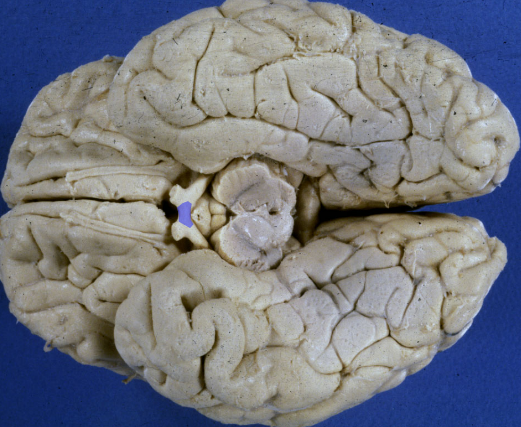

optic nerve

A lesion of the right optic nerve causes

optic tract

thalamus and the crus cerebri

A lesion of the right optic tract causes a complete loss of vision in the left hemifield:

contralateral “homonymous” hemianopsia.

(can see crus cerebri but not optic tracts yet)